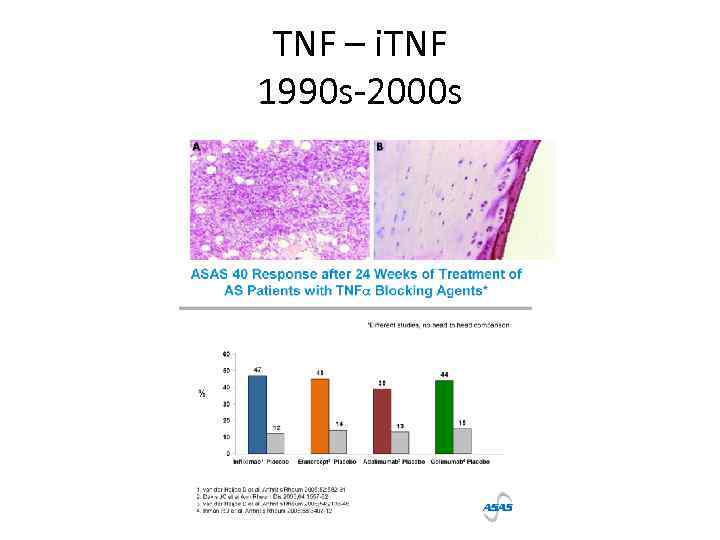

TNF – i. TNF 1990 s-2000 s